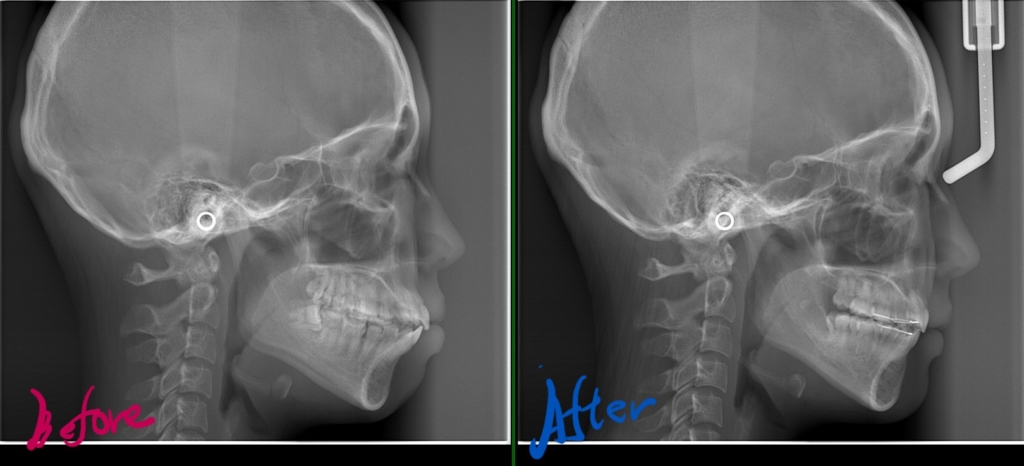

レントゲン写真で確認すると、

矯正後の状態をレントゲン写真で確認すると、

参考までに矯正治療前後の「レントゲン写真」と「口元の写真」を比較してみましょう。 見て一目瞭然に違いが分かると思います。